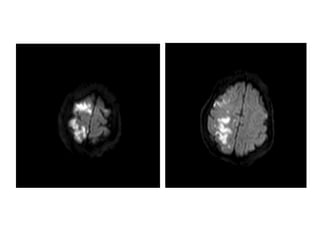

Acute (4 hours)

Infarction

Subtle blurring of gray-white

junction & sulcal effacement

Subacute (4 days)

Obvious dark changes &

“mass effect” (e.g.,

ventricle compression)

RR L L

Acute (4 hours) Infarction Subtleblurring of gray-white junction & sulcal effacement Subacute (4 days) Infarction Obvious dark changes & “mass effect” (e.g., ventricle compression) RR L L